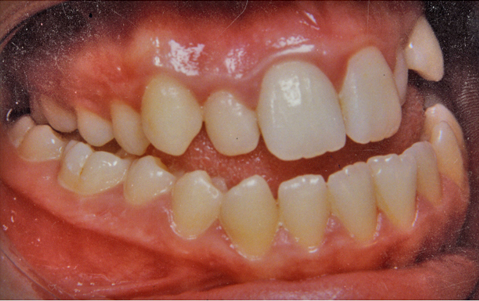

Tα άνω πρόσθια δόντια εξέχουν προς τα εμπρός πιο πολύ από τα κάτω πρόσθια